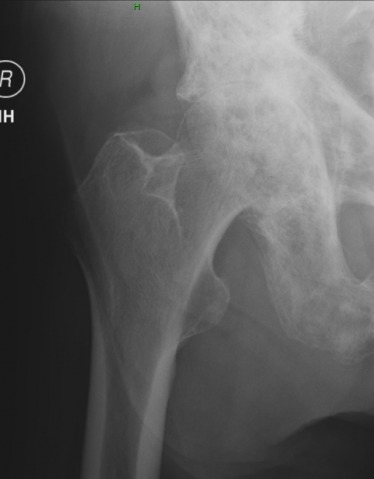

1. What are the main findings?

2. What are the differential considerations for the key finding?

3. What disorders most commonly produce a sclerotic Kohler's teardrop sign?